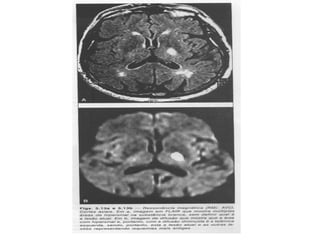

ETIOLOGIA

• Mecanismos Isquêmicos:

– Trombos, embolismos, problemas que diminuem pressão de perfusão

sistêmica (hipotensão sistêmica);

– O cérebro fica privado de glicose e oxigênio, prejudica o metabolismo

celular e leva a lesão e morte do tecido nervoso;

– A lesão isquêmica por trombos é chamada de infarto cerebral

aterotrombótico (ICE).

• Mecanismos Hemorrágicos:

– Causado por aneurismas ou tramas para dentro das áreas extravasculares

do cérebro;

– Resulta no aumento da pressão intracraniana (PIC);

– Hemorragia cerebral primária – espontânea, não traumática – vasos

pequenos enfraquecidos pela aterosclerose (provocam aneurismas);

– Hemorragia subaracnóide (HS) – sangramento para dentro do espaço

subaracnóide – aneurisma em amora ou sacular – afeta vasos grandes;

– Malformação arteriovenosa (MAV) – se caracteriza por emaranhado de

artérias e veias – a hemorragia pode ser subaracnóide ou intracerebral.